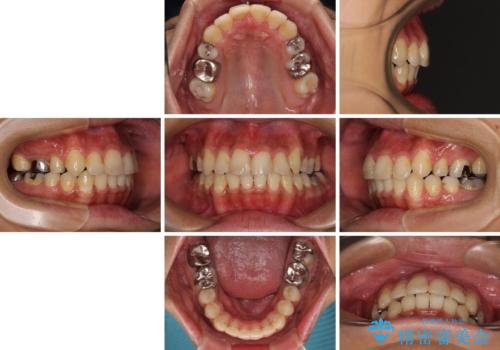

八重歯と開咬 ワイヤー装置での抜歯矯正

舌の突出癖により開咬となっていたため、突出癖改善のためのトレーニングをしっかりと行っていただき、予定の期間で無事に治療を終えることができました。